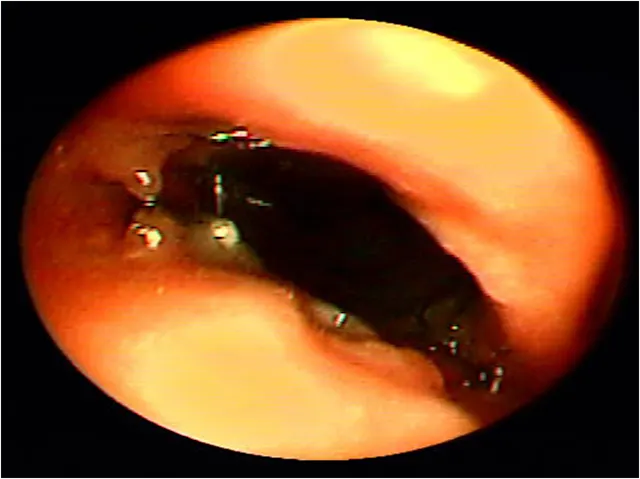

Tracheoscopy, the gold standard for diagnosing tracheal collapse, enables direct viewing of the trachea and mainstem bronchi, quantification of severity and extent of collapse, identification of concurrent inflammation, and collection of tracheal or bronchial samples for culture and cytology. With tracheoscopy, tracheal collapse can be categorized based on the Tangner and Hobson grading system with grades I, II, III, and IV characterized by 25%, 50%, 75%, and 100% collapse, respectively16 (Figure 2). Disadvantages include limited availability, cost, and need for general anesthesia. Because veterinary patients may be small, tracheoscopy is often performed under injectable anesthesia and without intubation; as such, ventilation cannot be assisted during the procedure, and oxygen must be supplemented through the endoscope or with an intratracheal catheter. Some dogs with severe tracheal collapse develop dyspnea and cyanosis during anesthetic recovery.

Endoscopic view of tracheal collapse: Grades I–IV (A-D) of tracheal collapse, respectively. Used with permission.23